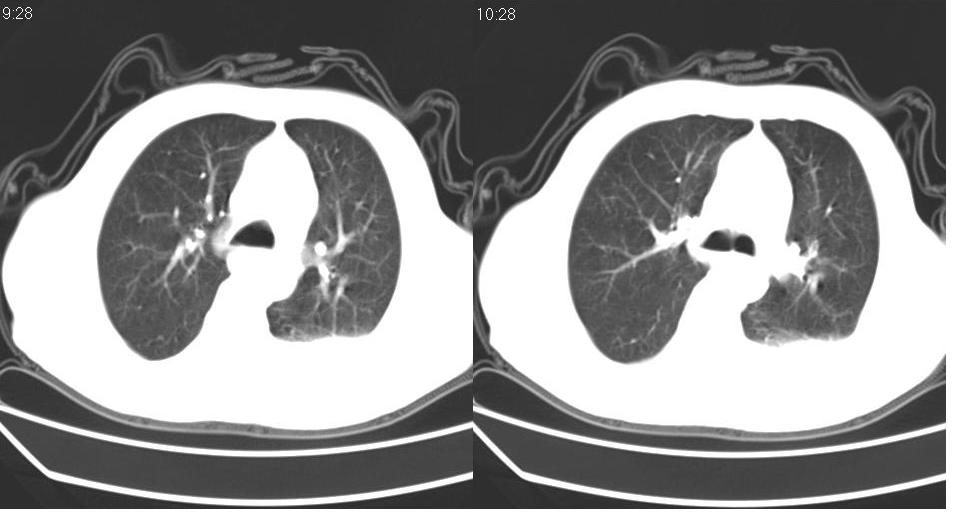

左肺下叶略萎陷、实变,内可见含气支气管征。左舌叶、中叶亦见少许斑片状高密度区,边界不清。纵隔未见肿大淋巴结影。

左下肺体积缩小,密度增高,见片增密影。边界模糊,见支气管充气像,肺门纵隔无异示,心脏气管左移,左侧胸腔少量积液。考虑肺部感染伴部分肺不张[有脑梗塞病史坠积性肺炎可能]

1、左肺下叶后基底段炎症并膨胀不全。

2、左侧胸腔积液。

左肺下叶体积缩小,成类楔形软组织影,其内可见部分含气支气管影,相应左侧肺门区未见明显肿块,考虑炎性病变,建议抗炎后短期复查

左下肺体积缩小,密度增高,并见大片状致密影,边界模糊,其内见支气管充气像,肺门纵隔无异常,心脏气管左移,左侧胸腔少量积液。考虑:左肺炎性病变伴不张。